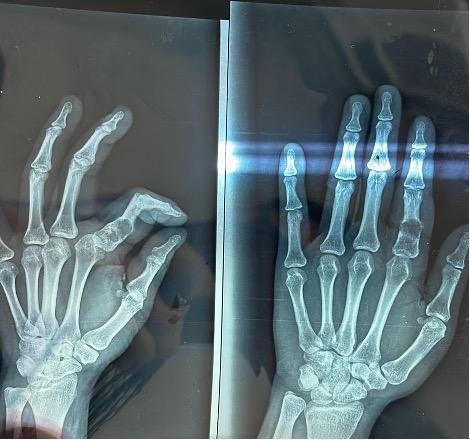

Case Report: We present three cases of hand enchondroma involving the phalanges in patients aged 20–37 years. Clinical features included fusiform swelling, pain, and, in one case, pathological fracture. Radiographs showed well-circumscribed lytic lesions with chondroid matrix. All cases were treated with intralesional curettage, cavity filling with cancellous autograft harvested from the olecranon, and prophylactic K-wire fixation. Histopathology confirmed enchondroma in each case. Postoperatively, patients underwent short-term immobilization followed by physiotherapy. At 12 weeks, all achieved full functional recovery with radiological consolidation and no recurrence or complications.

A 21-year-old male presented with a 2-month history of painless swelling of the left little finger, which gradually increased in size and caused mild discomfort on gripping. On examination, a fusiform, firm, non-tender bony swelling was palpable over the proximal phalanx with intact skin and preserved digital motion, though mild restriction of terminal flexion was noted. Radiographs revealed a well-circumscribed, expansile lytic lesion with chondroid matrix, consistent with enchondroma. Surgery was performed using a dorsal midline approach; intralesional curettage was followed by filling with cancellous autograft from the ipsilateral olecranon and prophylactic K-wire fixation. Histopathology showed lobules of mature hyaline cartilage containing small, uniform chondrocytes in lacunae, without nuclear atypia or mitoses, confirming benign enchondroma. At 12-week follow-up, radiographs showed complete graft incorporation, and the patient regained full pain-free range of motion with return to daily activities.

A 37-year-old female presented with 4 months of pain and swelling in the right index finger, interfering with writing and daily chores. Clinical examination revealed diffuse fusiform swelling of the proximal phalanx, mildly tender to palpation, with partial restriction of flexion at the proximal interphalangeal joint. Radiographs demonstrated a well-defined intramedullary lytic lesion with cortical thinning but no fracture. Surgical management involved curettage through a cortical window, cavity irrigation, and filling with morselized olecranon cancellous graft. Histopathological analysis confirmed enchondroma with typical cartilage lobules and absence of atypical features. The finger was immobilized in a below-elbow splint for 2 weeks, after which physiotherapy was commenced. At 10 weeks, the patient achieved full motion and reported complete resolution of pain, with no radiological evidence of recurrence (Fig. 1).

A 20-year-old female sustained trivial trauma to the left little finger, followed by acute pain, swelling, and deformity. Radiographs showed an enchondroma of the proximal phalanx complicated by a pathological fracture with cortical breach. A similar dorsal approach was employed; after curettage and grafting with olecranon cancellous bone, prophylactic K-wire fixation was used to stabilize the fracture site. Histopathology demonstrated mature cartilage with uniform chondrocytes, confirming enchondroma without evidence of malignancy. Sutures were removed at 2 weeks, and K-wires at 6 weeks, followed by physiotherapy. By 12 weeks, radiographs showed satisfactory union with graft consolidation. The patient achieved complete functional recovery, including grip and pinch strength, and resumed regular household activities without restriction.